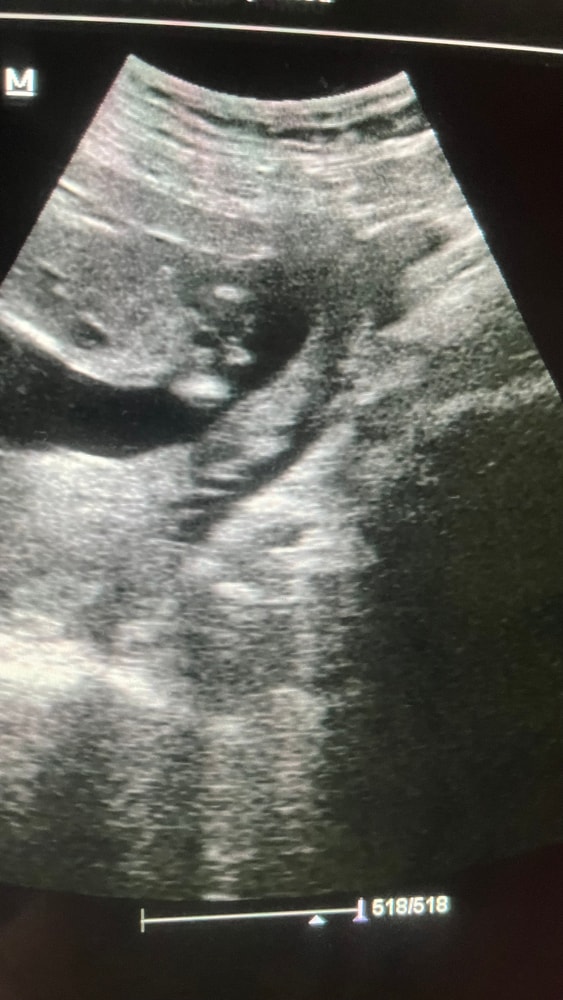

2 ,3 фото - сейчас, 14 недель и 3дня срок. Может кто понимает в этом?

пол ребенка виден?

Девочка у вас) Между ножек на таком сроке не смотрят, там будет одинаково, а сбоку явно девчонка)